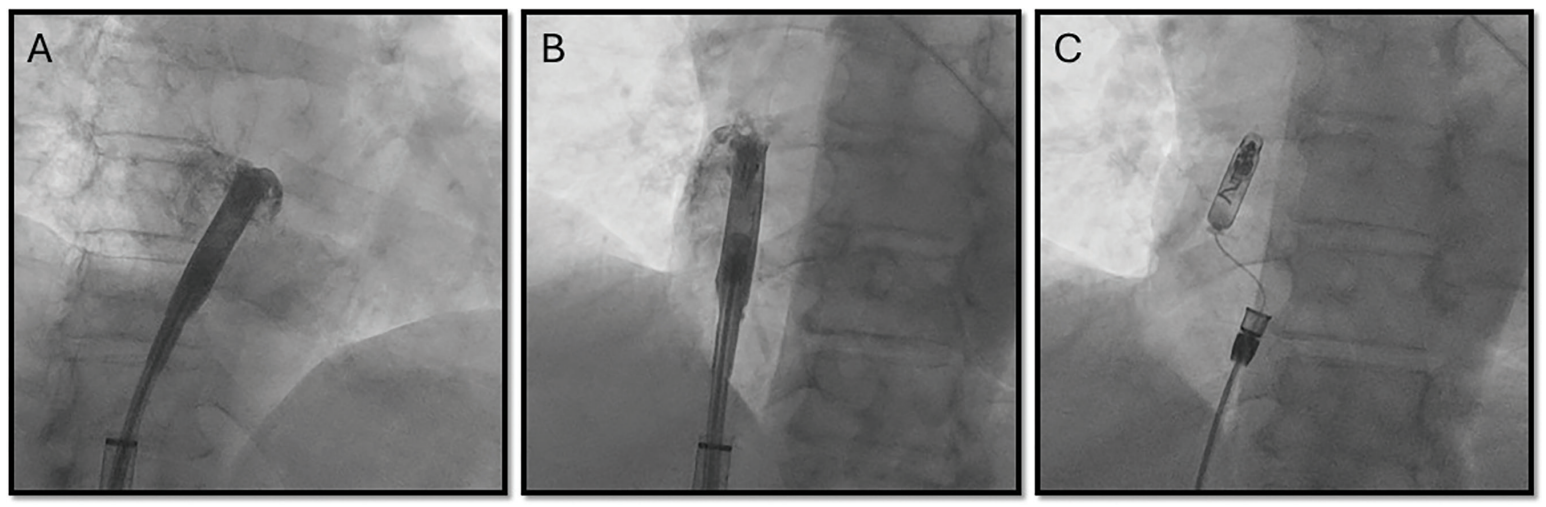

The procedure was performed in a cardiac electrophysiology laboratory under fluoroscopic guidance. Transfemoral venous access was obtained under sterile conditions, and the leadless pacemaker delivery system was advanced into the RA. To target the BB region, the system was advanced into the superior vena cava with the protected sleeve over the device. It was then withdrawn with anteroseptal deflection until the tip shifted toward the septal base of the RAA. The device was

then advanced under left anterior oblique (LAO) fluoroscopic view to direct the pacemaker toward the superior interatrial septum until the tip straightened along the RA roof, corresponding to the anatomical confluence of the interatrial septum and RA roof. Anterior positioning was confirmed in the right anterior oblique (RAO) view. Intracardiac contrast was injected in both views to verify localization at the anterior septal region (Figure 2) and mapping was performed prior to fixation displaying rapid P-wave upstrokes in leads II and III. Fixation was performed by screwing in the device with a half-body turn under anteroseptal deflection with the break. Once the torque of the half turn was fully conducted, the break was released while the device remained stable, and the remainder of the 1.5 total body turns were completed. Stability was confirmed by a tug test. Acute pacing and sensing thresholds were satisfactory, with atrial capture at 1.25 V @ 0.4 ms, impedance of 330 ohms, and sensing amplitude of 3.4 mV. Once parameters remained stable and fixation was confirmed, the tether was released and the delivery tool was withdrawn. Final fluoroscopic images in both LAO and RAO projections confirmed device placement at the junction of the RA roof and interatrial septum. The total procedure time was 36 minutes, with a fluoroscopy time of 5.3 minutes and radiation dose of 34.1 mGy.